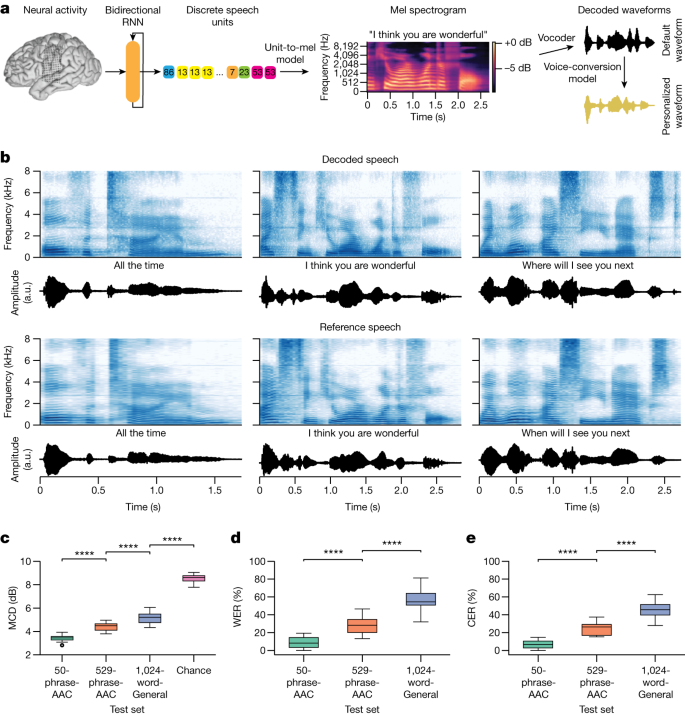

این دستگاه با استفاده از الکترودهای حساس و الگوریتمهای هوش مصنوعی سیگنالهای مغزی مرتبط با افکار گفتاری را ثبت میکند. مراحل اصلی عملکرد شامل:

ثبت سیگنالهای عصبی: از طریق الکترودهای غیرتهاجمی یا نیمهتهاجمی، فعالیت مغز ضبط میشود.

پردازش دادهها: سیگنالهای پیچیده مغزی به الگوریتمهای یادگیری ماشین داده میشوند.

ترجمه گفتار درونی: مدل هوش مصنوعی الگوهای مغزی را به کلمات یا جملات قابل خواندن تبدیل میکند.

هوش مصنوعی پیشرفته: الگوریتمهای یادگیری ماشین توانایی تشخیص الگوهای پیچیده مغزی را دارند.

دقت محدود: ترجمه گفتار درونی هنوز صددرصد دقیق نیست و به تمرین و آموزش فرد وابسته است.

نیاز به آموزش فردی: هر مغز الگوهای منحصر به فردی دارد و مدلها باید با کاربر تطبیق داده شوند.